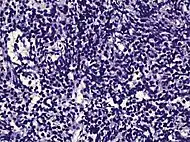

| Subdiagnosis | Relative incidence | Image | Microscopic characteristics | Immunohistochemistry | Gleason scoring | ||

| Acinar adenocarcinoma - 93%[2] | Adenocarcinoma (not otherwise specified/ conventional/ usual acinar)[3] |

77%[notes 2] | 54%[notes 2] | ![]() |